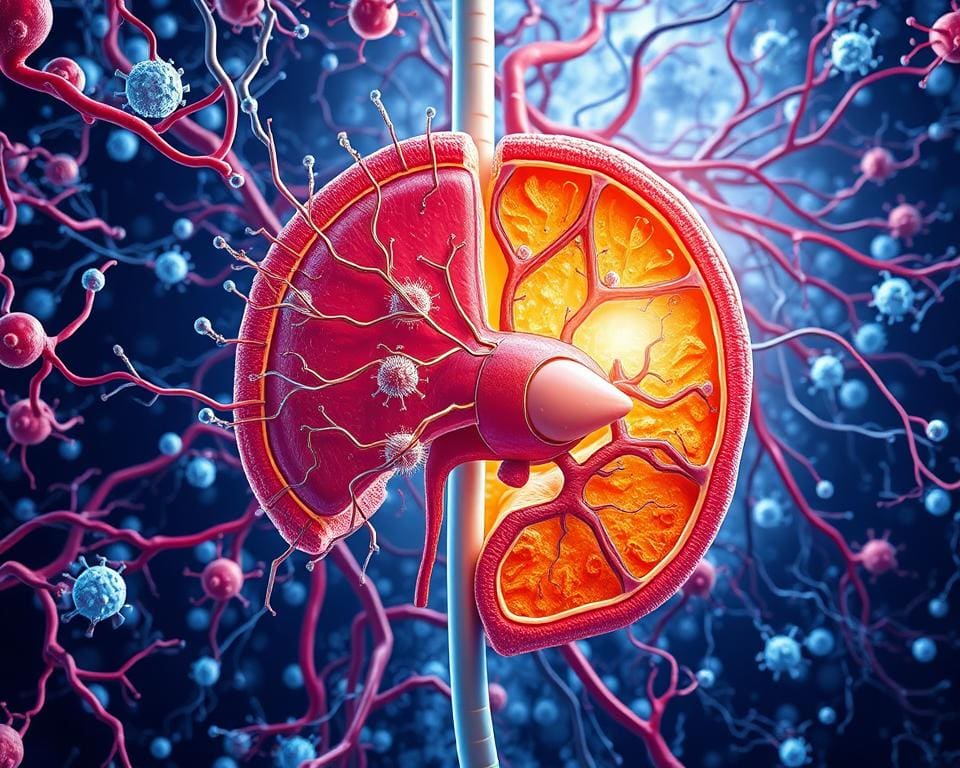

Das Immunsystem besteht aus mehreren Schlüsselkomponenten, die zusammenarbeiten, um die Immunabwehr des Körpers zu gewährleisten. Zu diesen Komponenten gehören vor allem die weißen Blutkörperchen, die Lymphknoten und die Milz. Jedes dieser Elemente spielt eine wichtige Rolle bei der Bekämpfung von Infektionen und der Aufrechterhaltung der Gesundheit.

Die Lymphknoten und die Milz sind wesentliche lymphatische Organe, die eine zentrale Rolle im Immunsystem spielen. Lymphknoten agieren als Filterstationen, in denen schädliche Substanzen aus der Lymphe herausgefiltert werden. Sie sind entscheidende Knotenpunkte, an denen Immunantworten initiiert werden. Die Milz trägt zur Produktion und Aktivierung von weißen Blutkörperchen bei, während sie gleichzeitig die Blutzellen überwacht und abnormale Zellen entfernt.